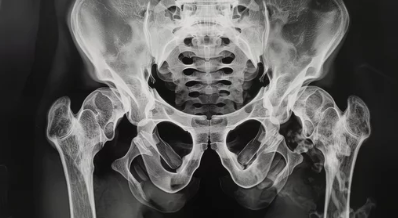

1. 엉덩이 통증이 발생하는 해부학적 구조 이해

✅ 엉덩이 구조는 어떻게 되어 있을까?

엉덩이는 크게 다음 세 가지 구조로 나뉩니다:

- 관절 및 뼈: 고관절, 천장관절, 좌골, 미추(꼬리뼈) 등